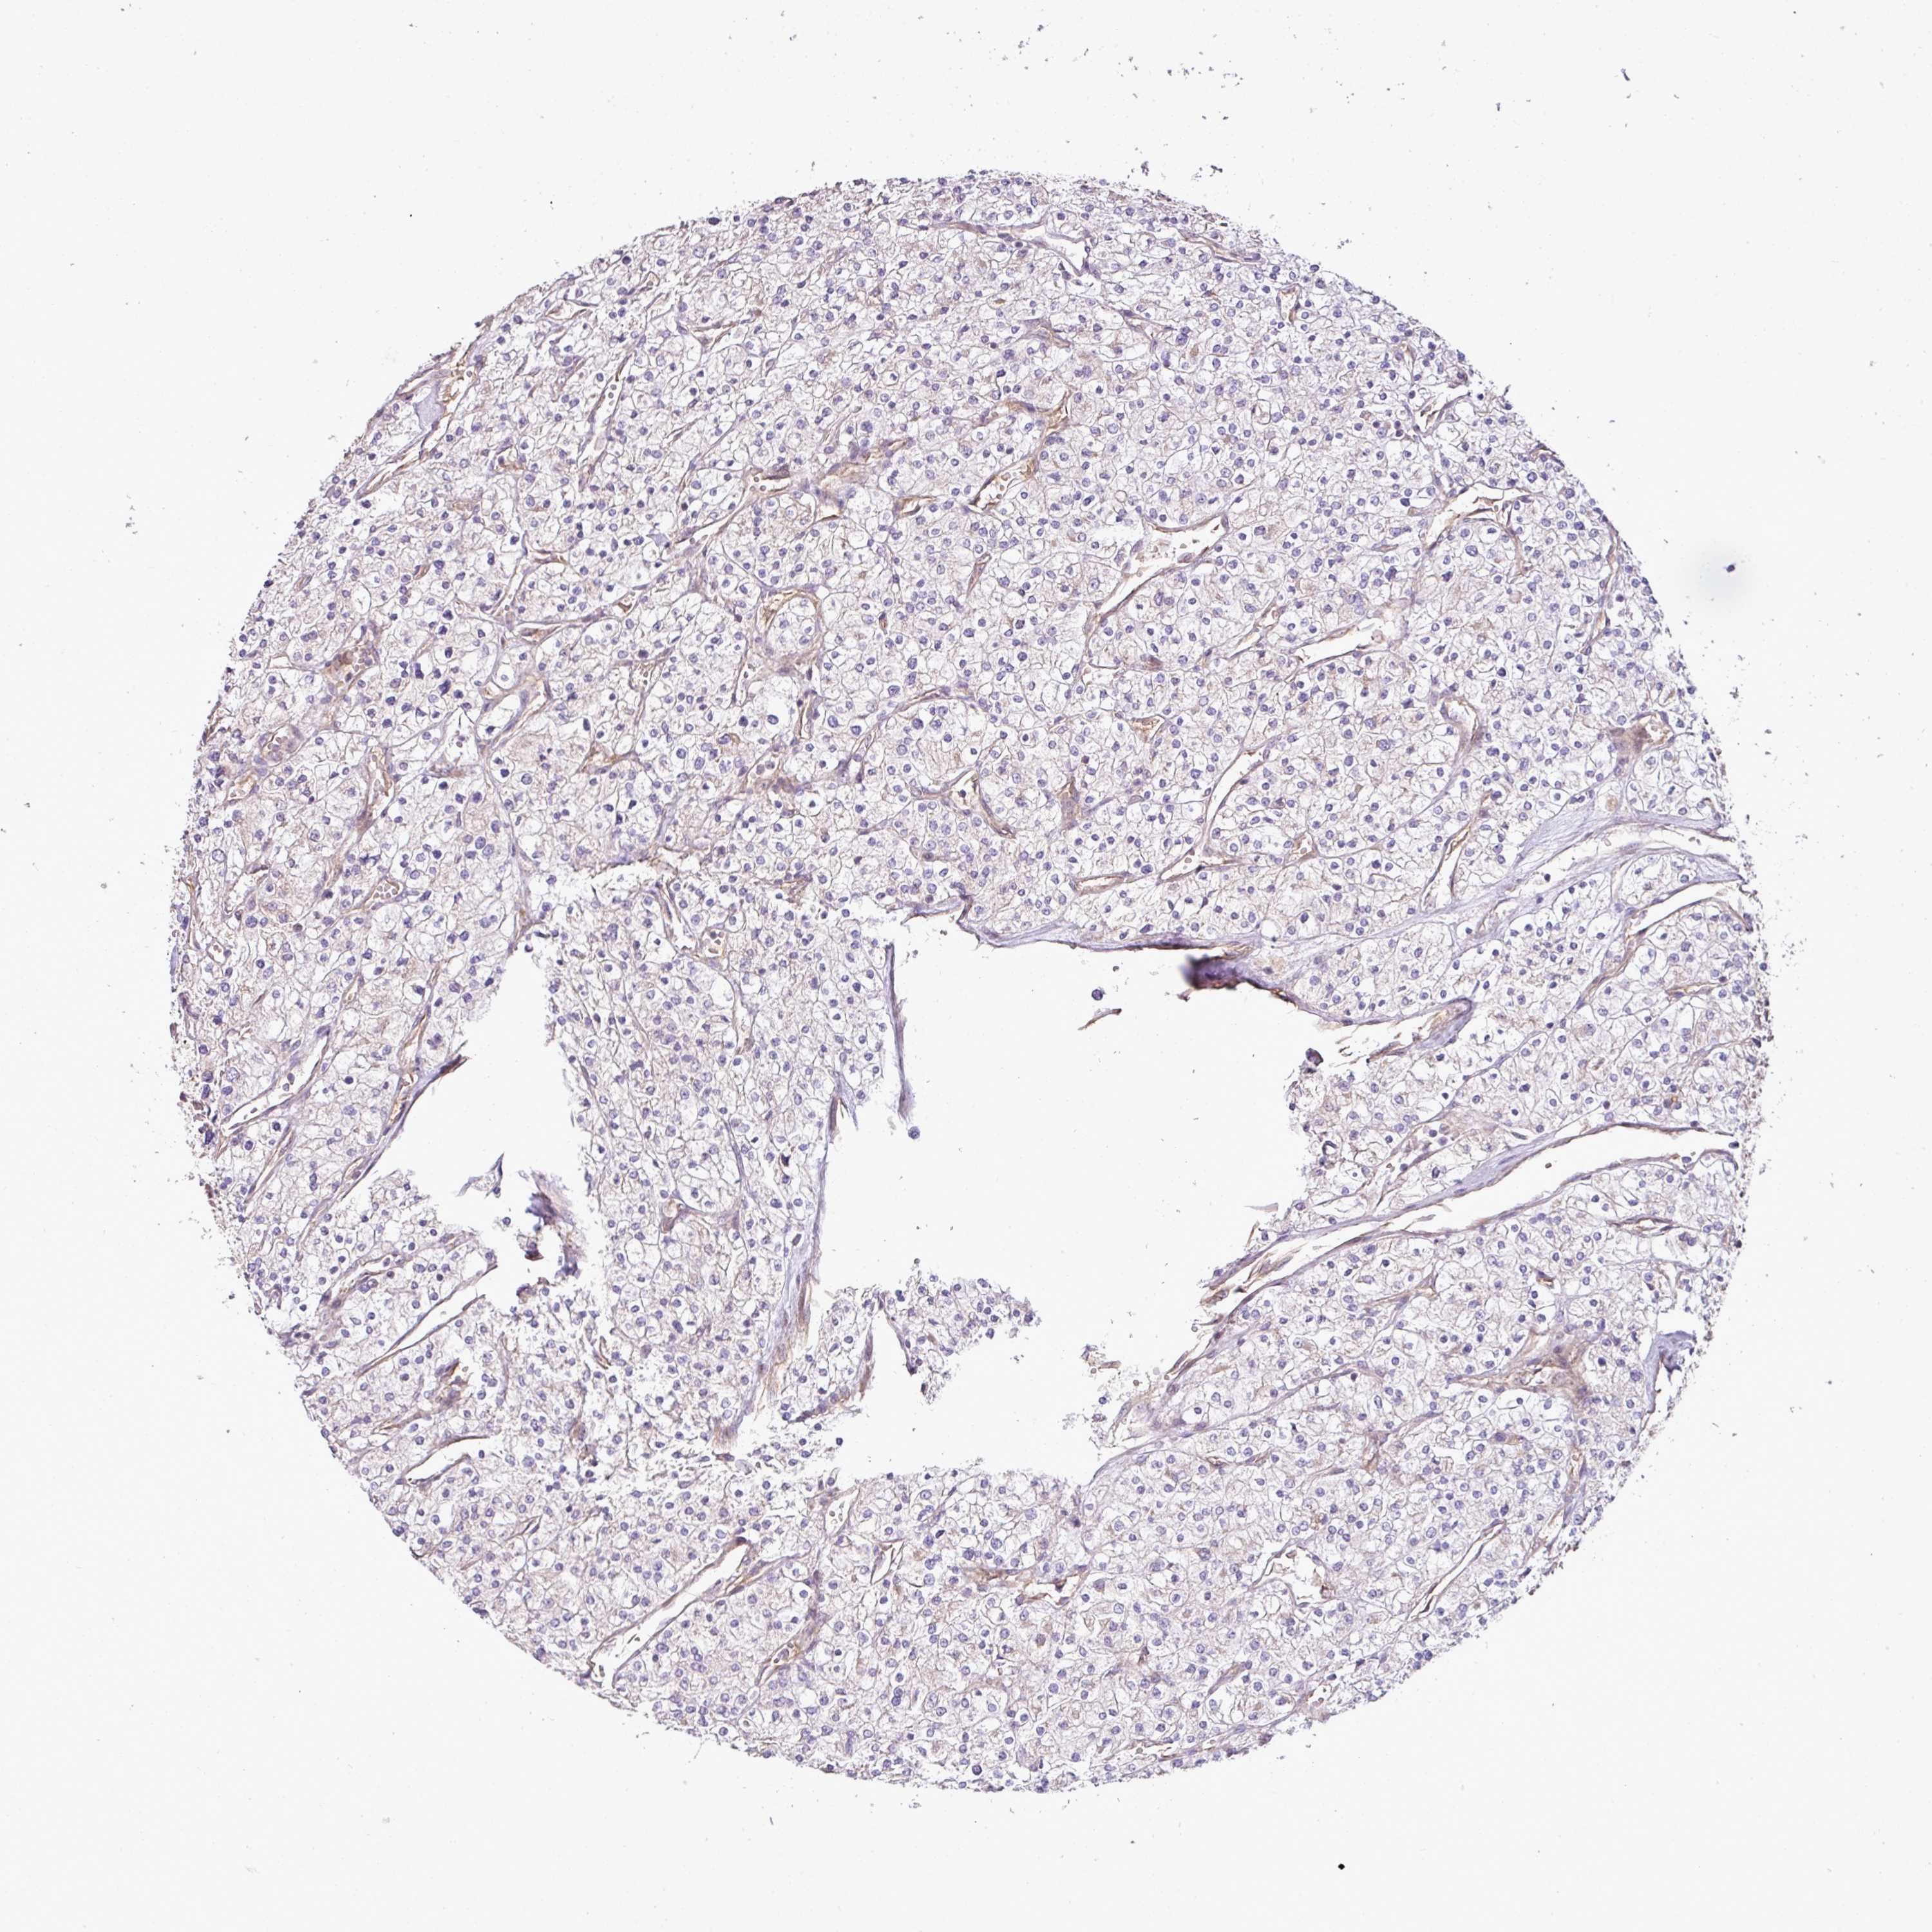

KIDNEY RENAL CLEAR CELL CARCINOMA (TCGA) - Interactive survival scatter ploti

The Survival Scatter plot shows the clinical status (i.e. dead or alive) for all individuals in the patient cohort, based on the same data that underlies the corresponding Kaplan-Meier plots. Patients that are alive at last time for follow-up are shown in blue and patients who have died during the study are shown in red.

& Survival analysisi

Kaplan-Meier plots summarize results from analysis of correlation between mRNA expression level and patient survival. Patients were divided based on level of expression into one of the two groups "low" (under cut off) or "high" (over cut off). X-axis shows time for survival (years) and y-axis shows the probability of survival, where 1.0 corresponds to 100 percent.

COX18 is not prognostic in Kidney Renal Clear Cell Carcinoma (TCGA)

TCGA RNA samplesi

RNA-seq data is reported as average FPKM (number Fragments Per Kilobase of exon per Million reads), generated by the The Cancer Genome Atlas (TCGA) .

Normal distribution across the dataset is visualized with box plots, shown as median and 25th and 75th percentiles. Points are displayed as outliers if they are above or below 1.5 times the interquartile range. FPKM values of the individual samples are presented next to the box plot.

Average pTPM 0.6

Number of samples 521